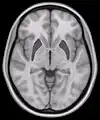

This is a transverse section of the striatum from a structural MR image. The striatum includes the caudate nucleus (top) and putamen (right) and the globus pallidus (left).